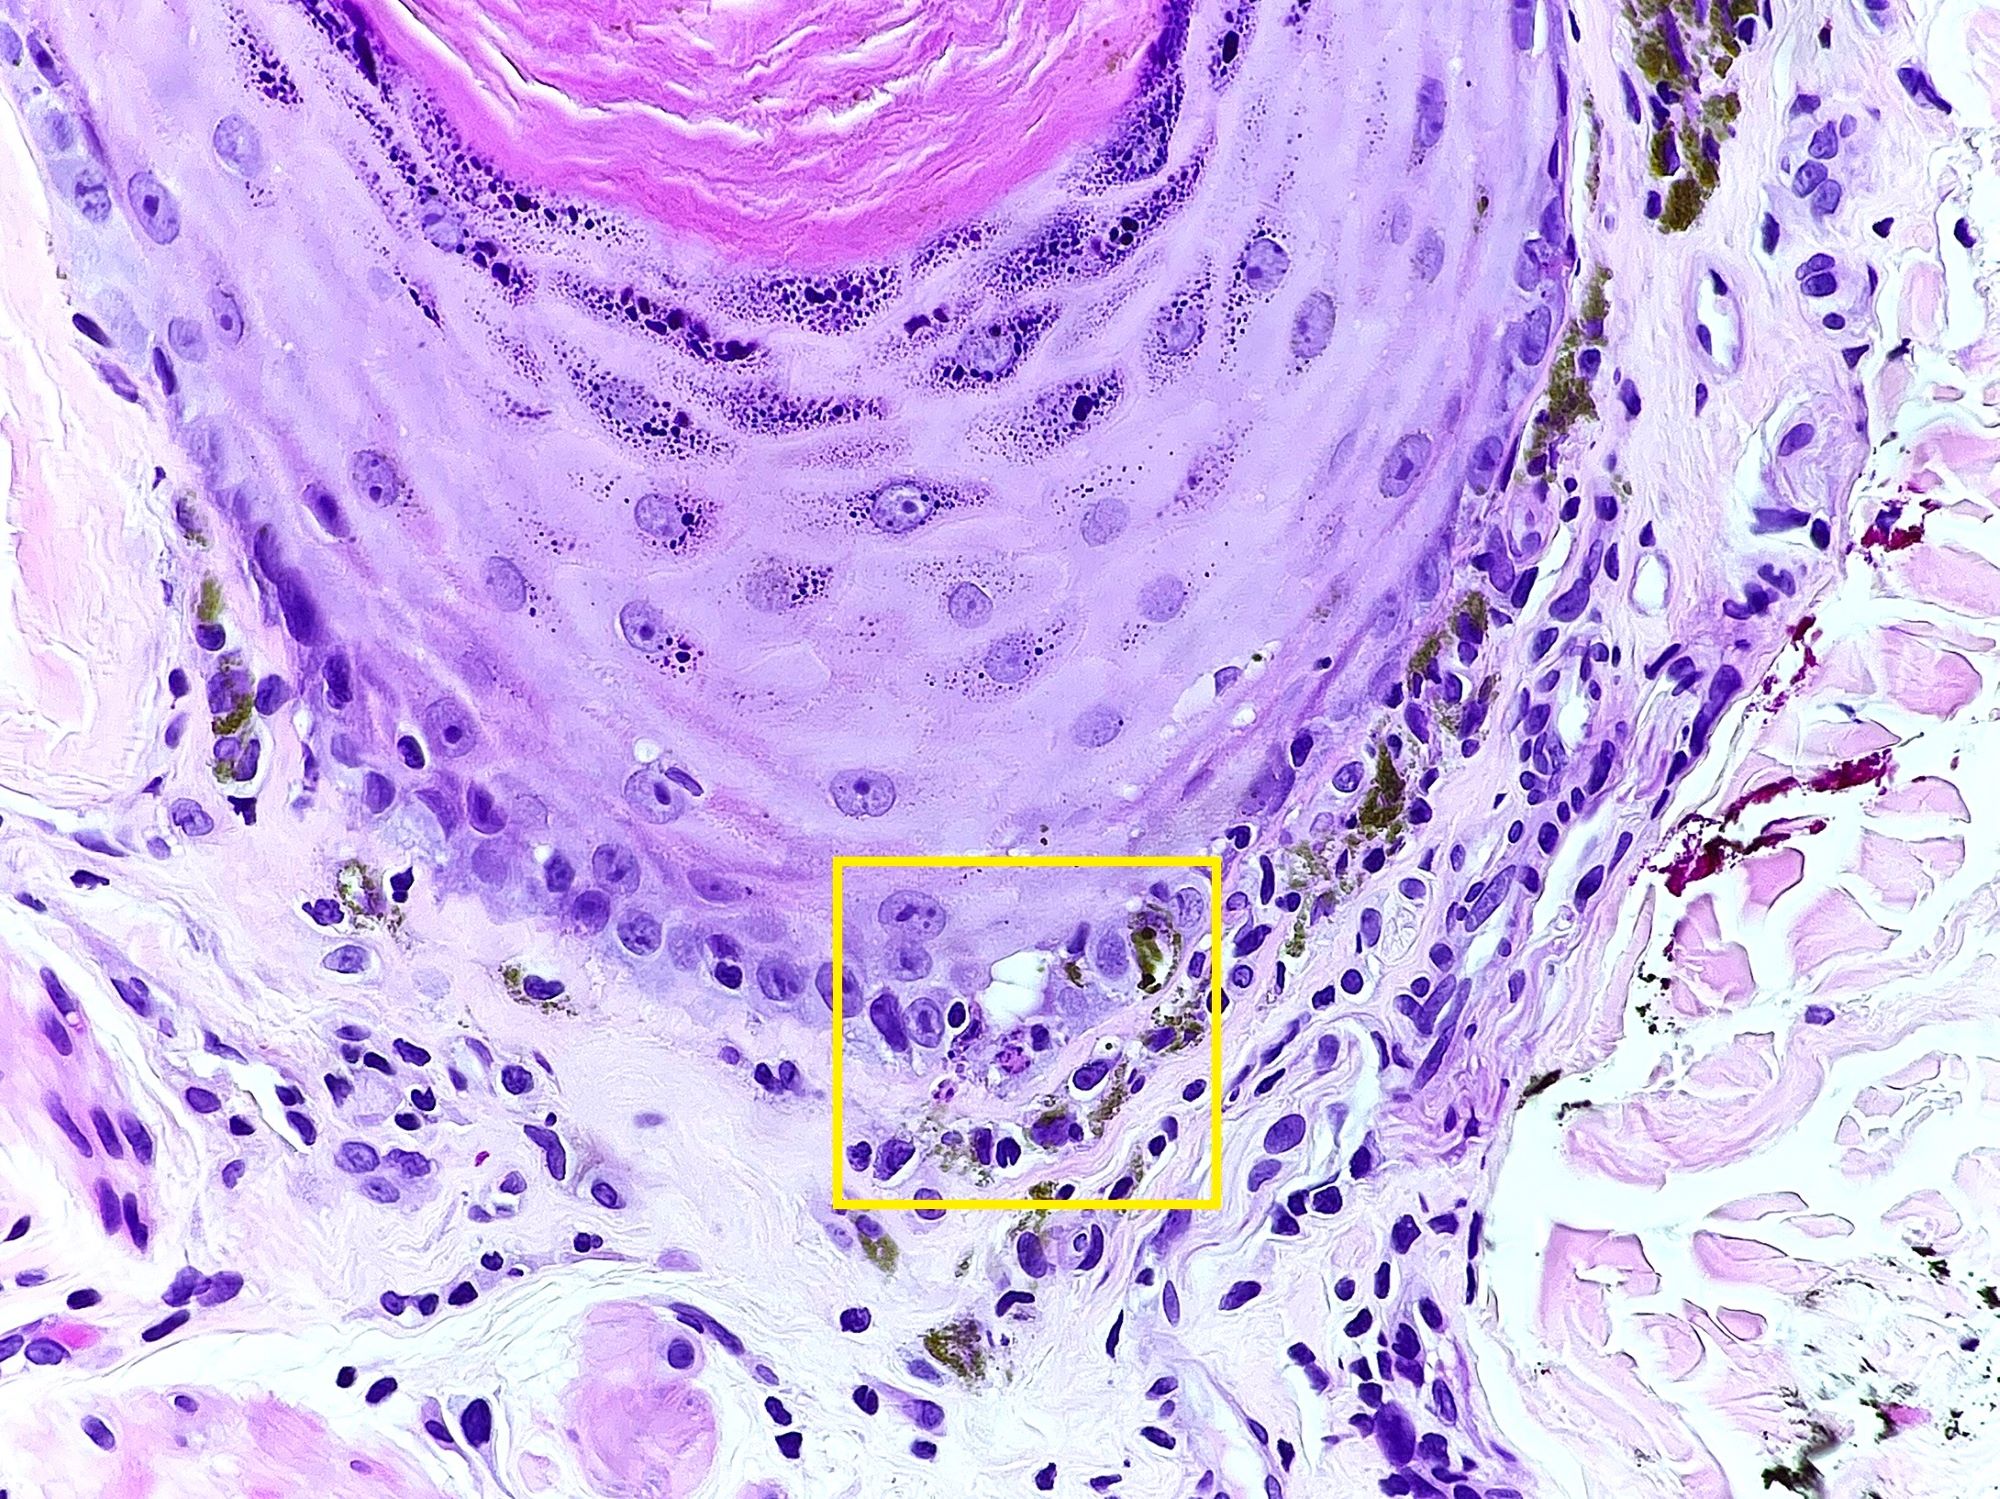

- Chronic GVHD (Biol Blood Marrow Transplant 2015;21:589, Patterson: Weedon's Skin Pathology, 4th Edition, 2015)

- Chronic lichenoid GVHD

- Acanthosis, orthohyperkeratosis, parakeratosis with hypergranulosis

- Underlying band-like lymphocytic infiltrate with basal layer vacuolization and apoptotic keratinocytes

- Periadnexal inflammation can be present

- May be difficult to distinguish from lichen planus without clinicopathologic correlation; satellite cell necrosis is the most helpful clue in GVHD biopsies to distinguish it from lichen planus

- Rare variants: psoriasiform

- Psoriasiform epithelial hyperplasia

- Subtle vacuolar interface changes

- Satellite cell necrosis (Am J Dermatopathol 2018;40:511)

- Chronic lichenoid GVHD

Microscopic (histologic) images

Contributed by Silvija P. Gottesman, M.D. and Ohoud Aljarbou, M.D.